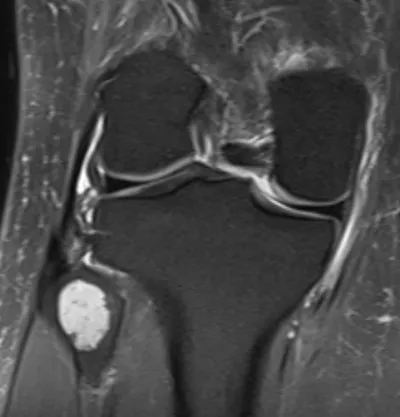

Browse 8 medical images tagged with benign. This collection includes various imaging modalities for medical education and reference.

- This collection contains 8 radiology images related to benign, including various imaging modalities such as X-rays, MRIs, CT scans, and ultrasound images commonly used in medical diagnosis and education.